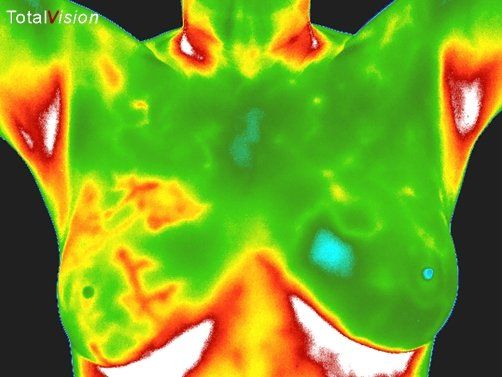

Literally, thermography means “heat picture.” Medical thermography maps the heat patterns of the human body using a digital thermal imaging camera.

Modalities like MRI’s, CT Scans, Ultrasound and Mammography see anatomy, or structure. Thermography is a test of physiology or function.

Medical thermography detects the heat associated with inflammation or increased blood flow. Inflammation is early in the disease process and is the root of pain and disease!

Medical thermography is, therefore, most often used as a discovery tool for preventive health, but it also has diagnostic applications as well.

Why Use Thermography for Breast Health Imaging?

The chart below is representative of an average growth pattern of the typical slow-growing breast tumor. Most doctors agree, and even tell their breast cancer patients that they have had the growth for 8 or 10 years. Thermography can see increased heat from the blood supply that feeds a tumor in its infancy. The only way to detect it at that stage is to establish a thermographic baseline and monitor every year for the real early signs!

Mammograms are a good tool for determining the exact location of a developed tumor, but it is not an early warning system, which some women assume that it is. The real danger of breast cancer is whether cancer has spread to a vital organ. If it is going to spread, it has had many years to do so. Women deserve earlier detection, and this is it.

Thermography can offer the opportunity to change a person’s health history. We believe prevention is preferable to disease management.